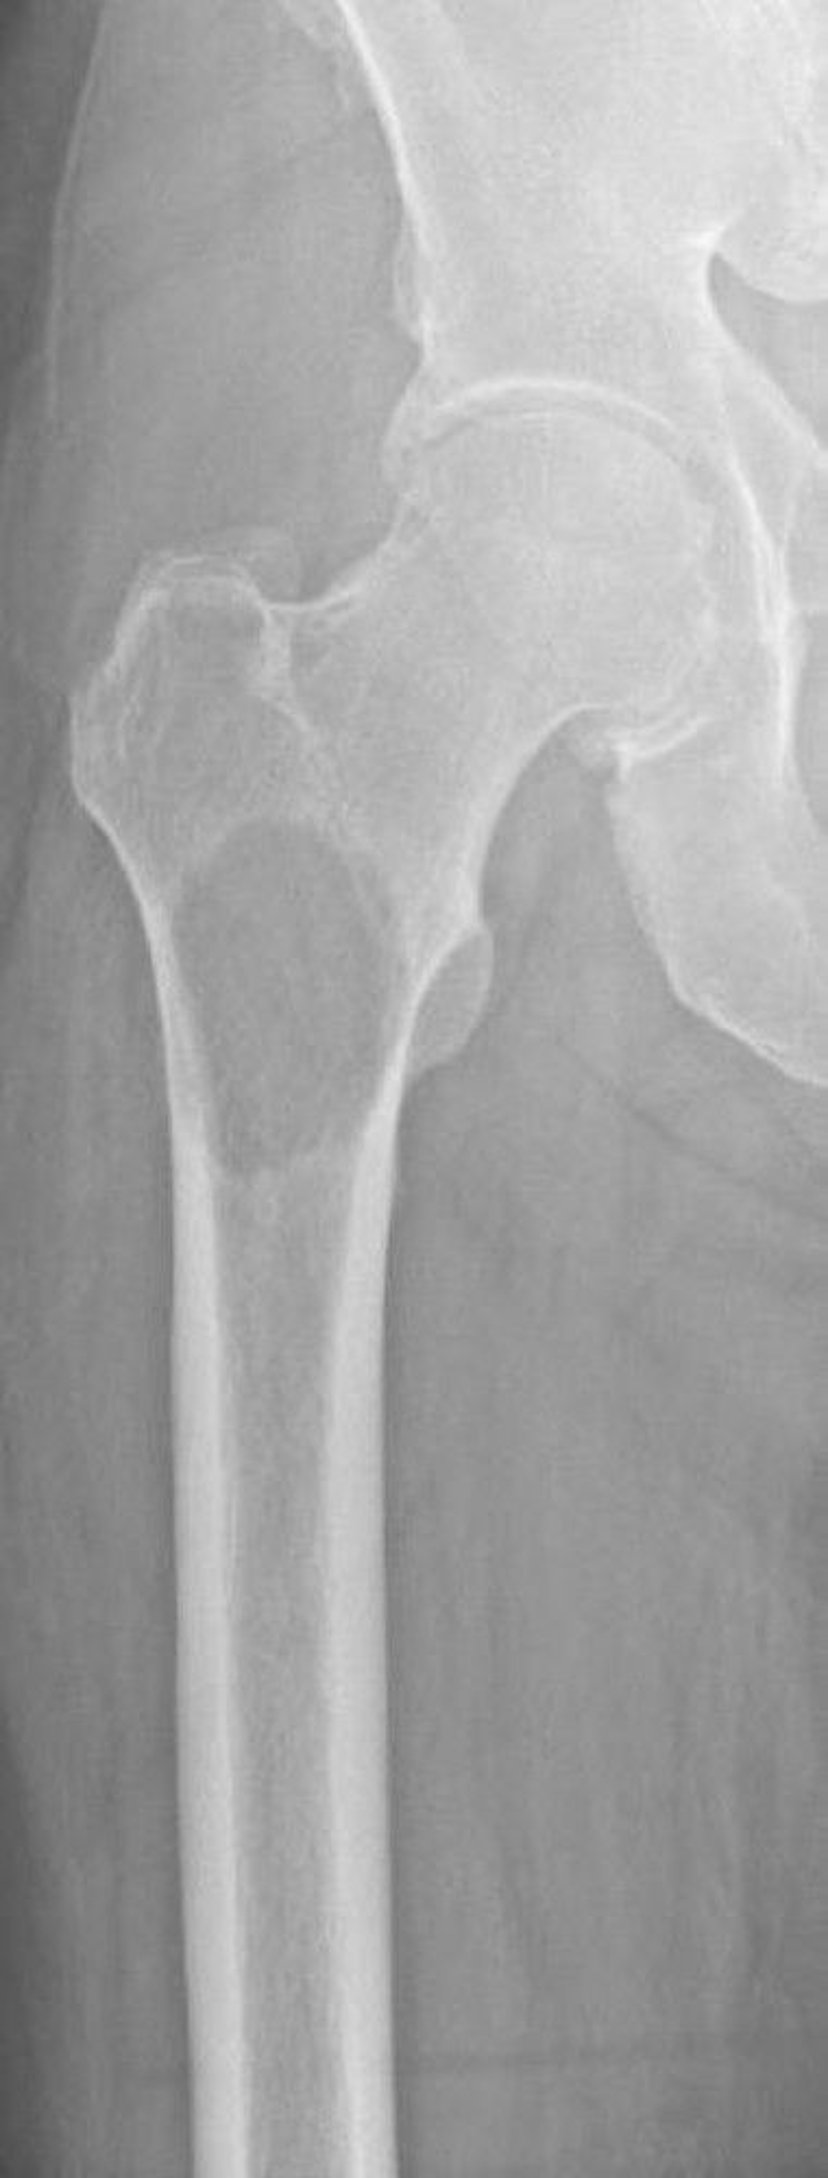

大腿骨近位部の溶骨性転移

この画像には,腎細胞癌に続発した転移により大腿骨近位部に発生した骨破壊が写っている。骨破壊の部位および範囲により,骨折のリスクが極めて高くなる(切迫骨折)。

Image courtesy of Michael J.Joyce, MD, and David M.Joyce, MD.